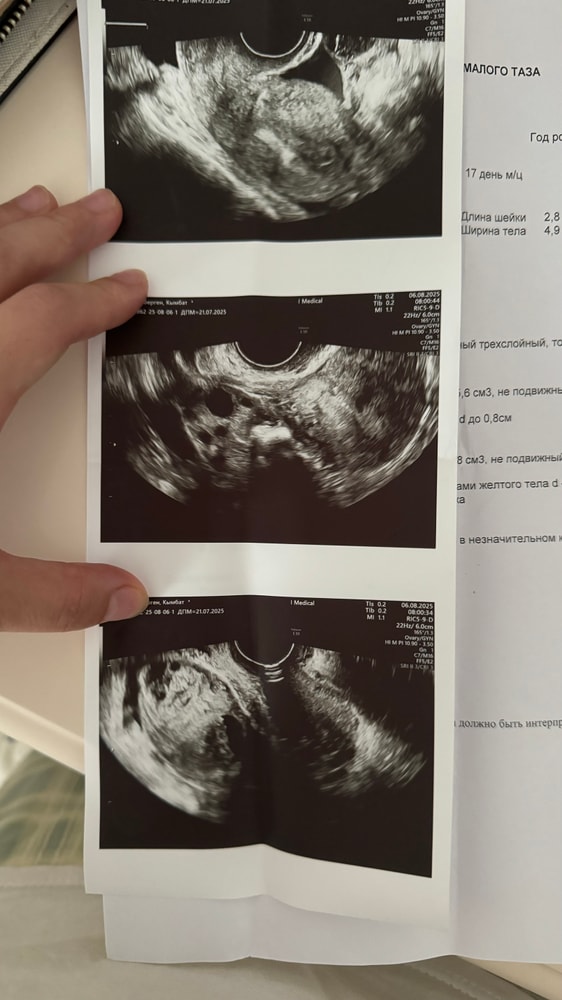

Ильмира, первый узи 1 августа было Дф 2,2 см и сразу кололи 10 тысяч хгч обычный …

Потом на 1-2-3 числа Па

И 4 числа на узи сказали что О еще не было Дф не лопнул ,и в этот же день опять 10 тысяч кололи но уже Пуберген аналог Овитреля ,Хгч какое нашла такое кололи 😅и вот спустя 1-2 дня сегодня на узи увидели Жт ))